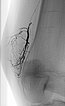

The radiographic overview after embolization of the AV fistulas shows the selective cast specimen of the radiopaque embolic agent filling the fistulas.

In the final overview digital subtraction angiography after embolization, the fistulas are completely occluded.